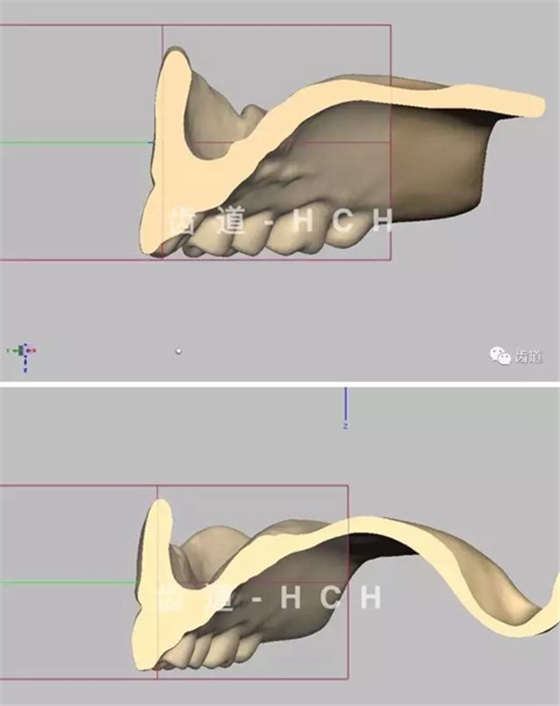

標(biāo)準(zhǔn)全口義齒模型截圖 科貿(mào)嘉友收錄